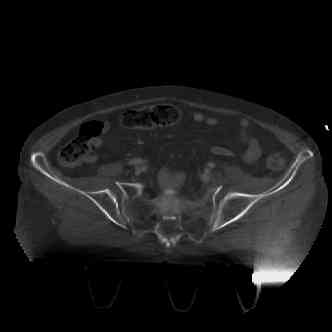

attached are several CT cuts. please let me know if you need more. the CT is pre-pelvic ex-fix placement.